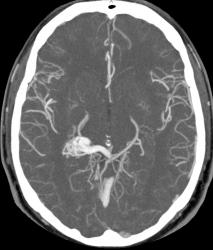

Предсталяю артериовенозную аневризму. Может кому-нибудь будет интересно.

Виден клубок неправильно развитых сосудов, питающихся от задней мозговой артерии и дренирующийся в прямой синус. Перифокальных изменений нет.

Черная стрелка - питащий сосуд - задняя мозговая артерия, зеленая - дренирующая вена к прямому синусу, красная - прямой синус.

Это очень интересный вопрос. Локализация мальформации для развития эписиндрома подходящая - височная область. Так что вполне вероятно, что эписиндром вызван мальформацией. Чаще сосудистые мальформации проявляют себя при возникновении кровоизлияния в прилегающие отделы мозга с соответствующей очаговой симптоматикой.

Я чуть увеличил фрагменты изображений с "патологическим состоянием"

Очень наглядна видна сосудистая мальформация.

Питание идет из гипертрофированных задней мозговой и средней мозговой артерий (красные стрелки), дренирование в основном в верхний сагиттальный синус (синий кружок). Дренирующая вена - синие стрелки.